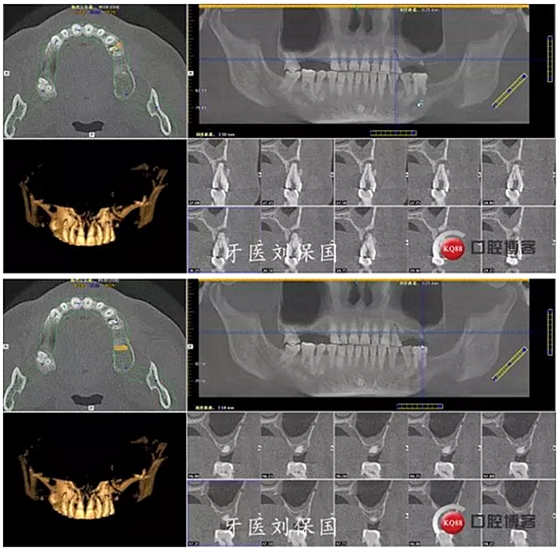

1.術(shù)前CT: